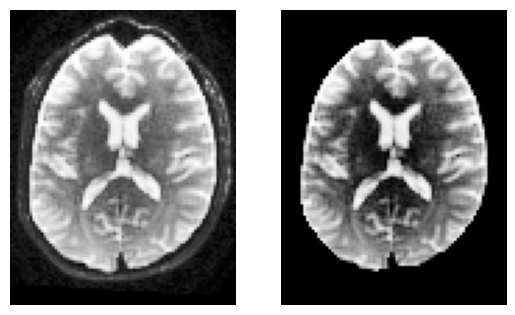

To keep things simple, we’ll compute a brain mask using median_otsu.

This function is inspired from Mrtrix’s bet which has default values median_radius=3, numpass=2. However, from tests on multiple 1.5T and 3T data from GE, Philips, Siemens, the most robust choice is median_radius=4, numpass=4 (default)

sli = data.shape[2] // 2

plt.subplot(1, 2, 1).set_axis_off()

plt.imshow(histeq(data[:, :, sli,0].astype("float")).T, cmap="gray", origin="lower")

plt.subplot(1, 2, 2).set_axis_off()

plt.imshow(histeq(b0_masked[:, :, sli,0].astype("float")).T, cmap="gray", origin="lower")

<matplotlib.image.AxesImage at 0x7f0937f693d0>

../_images/134d1f5dee31b52cabc8a32b8dc3935cef3d5ddc586efe41ec7b3e9496277e32.png